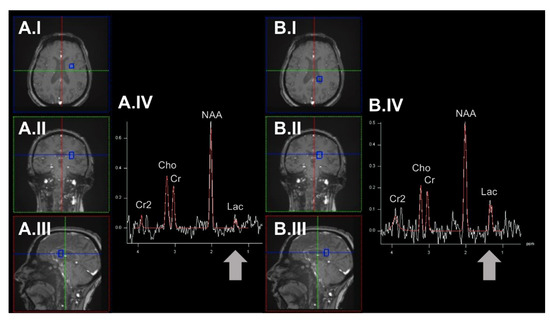

- Saito, S.; Takahashi, Y.; Ohki, A.; Shintani, Y.; Higuchi, T. Early detection of elevated lactate levels in a mitochondrial disease model using chemical exchange saturation transfer (CEST) and magnetic resonance spectroscopy (MRS) at 7T-MRI. Radiol. Phys. Technol. 2019, 12, 46–54. [Google Scholar] [CrossRef]